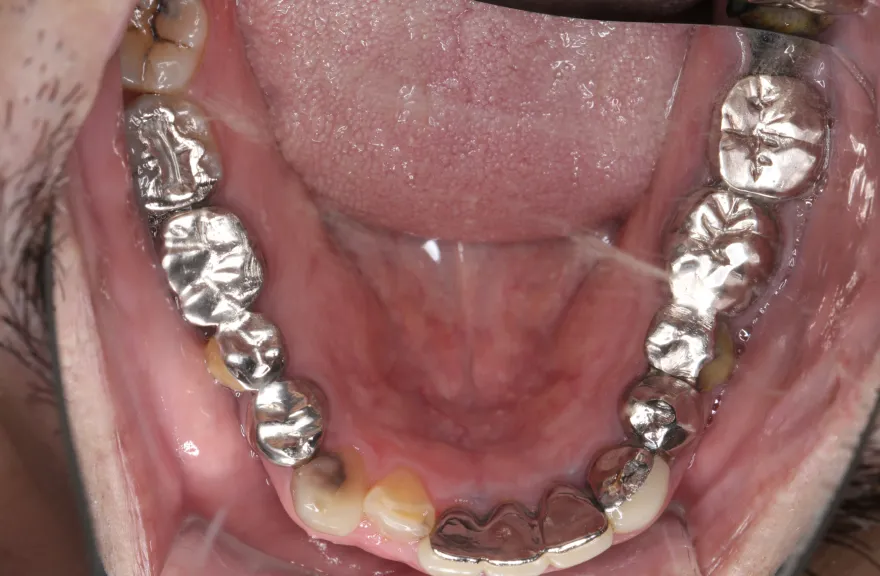

【治療例 2】金属を白くしたい63歳

右上の奥歯が取れたということで来院されました。

各所の金属は昔に治療されたもので、外してみるとどれも虫歯になっていました。

一つずつ虫歯治療を行い、インプラント治療、矯正治療を並行して行いました。 - 治療費用・方針

写真の通りに治療を終了いたしました。

各所虫歯に侵食されていましたが、歯を残すことができたのでインプラントの数をおさえることができました。

下の前歯が先天的に1本欠損しており、そのため噛み合わせを構築することが難しいケースでした。矯正治療を併用することで前歯と奥歯をバランスよく噛ませることに成功しました。